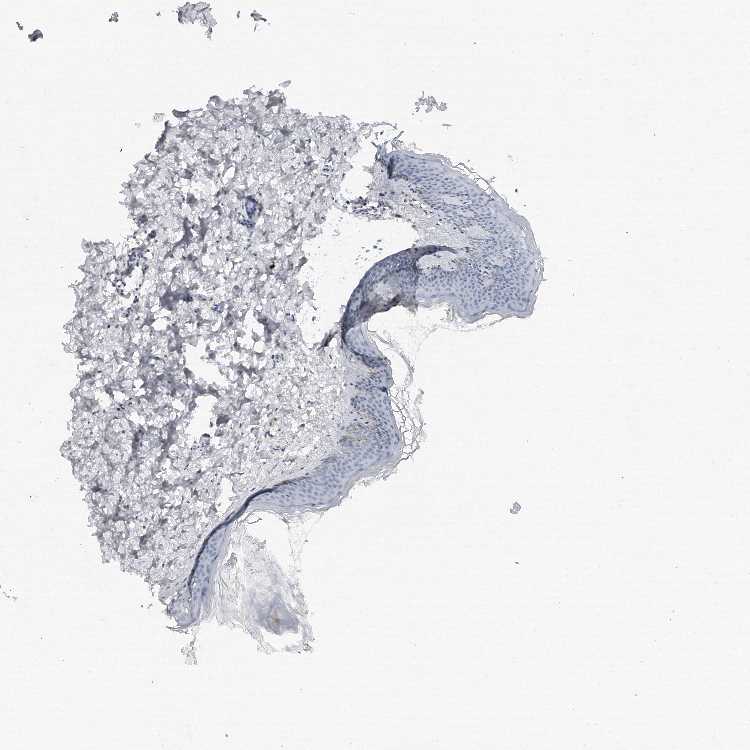

SKIN 1 - Antibody stainingi

Antibody staining in the annotated cell types in the current human tissue is reported as not detected, low, medium, or high, based on conventional immunohistochemistry profiling in selected tissues. This score is based on the combination of the staining intensity and fraction of stained cells.

Each image is clickable and will lead to virtual microscopy that enables deeper exploration of all samples and also displays staining intensity scores, fraction scores and subcellular localization as well as patient and tissue information for each sample.

Antibody HPA023559Antibody HPA023564Antibody HPA044971Antibody CAB031916

Langerhans Not detectedLowNot detectedNot detected

Fibroblasts MediumMediumMediumNot detected

Keratinocytes LowLowLowNot detected

Melanocytes MediumNot detectedMediumNot detected

SKIN 2 - Antibody stainingi

Epidermal cells LowNot detectedMediumNot detected